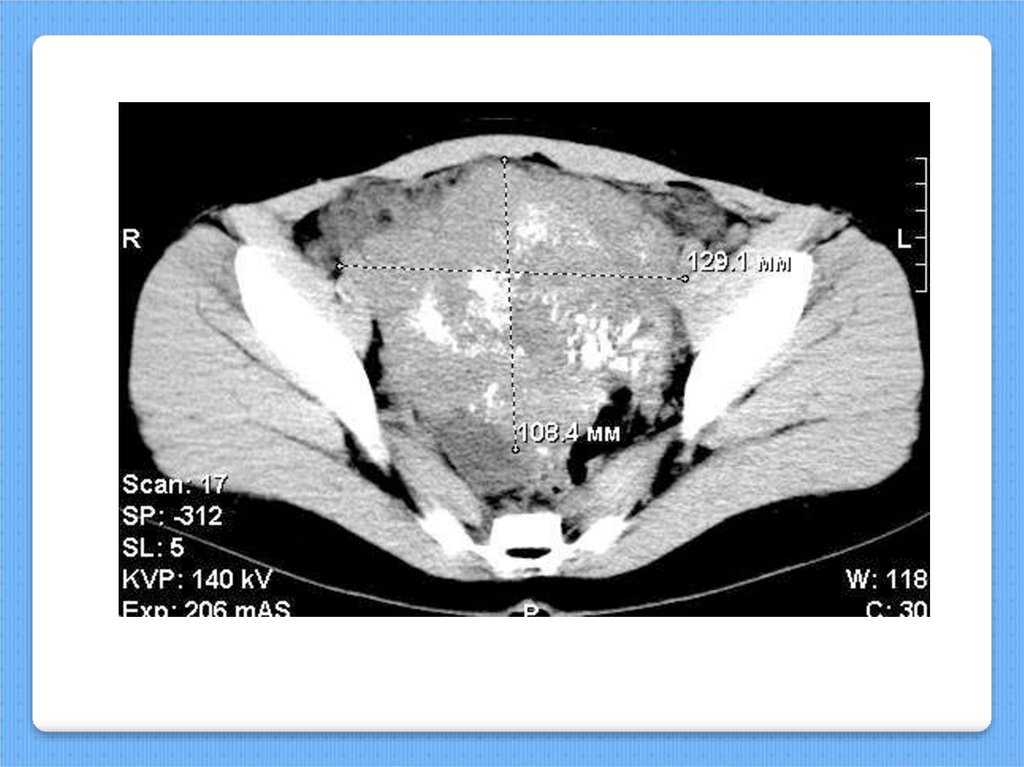

Левого

яичника

17.

Дисгерминома-1